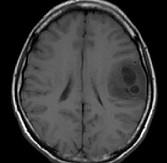

问题 女,33岁,三个月前有右上肢及右颜面部麻木,伴耳鸣及头昏,请根据所提供图像,选择最可能的诊断()

选项 A.脑脓肿 B.星形细胞瘤 C.脑结核 D.脑转移瘤 E.脑血吸虫病

答案 B